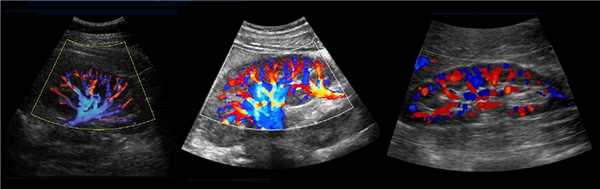

Рисунок. В воротах почки главная почечная артерия делится на пять сегментарных: задняя, верхушечная, верхняя, средняя и нижняя. Сегментарные артерии разделяются на междолевые артерии, которые располагаются между пирамидками почки. Междолевые артерии продолжаются в дугообразные → междольковые → приносящие артериолы клубочков → капиллярные клубочки. Кровь от клубочка отходит по выносящей артериоле в междольковые вены. Междольковые вены продолжаются в дугообразные → междолевые → сегментарные → главную почечную вену → нижнюю полую вену.

Рисунок. В норме при ЦДК сосуды почек прослеживаются до капсулы (1, 2, 3). Главная почечная артерия входит через ворота почки, добавочные артерии из аорты или подвздошной артерии могут подходить у полюсов (2).